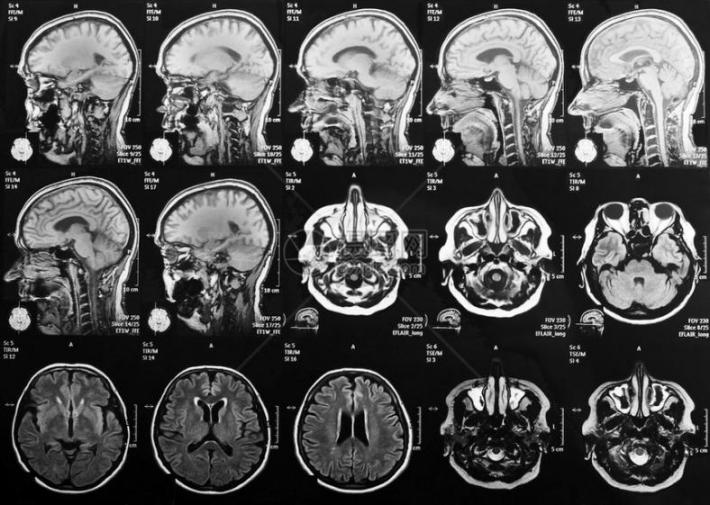

探密脑科学⑤|磁共振如何带我们看见大脑的思考?

我们每天都在思考,但思考时大脑里发生了什么?利用磁共振成像设备(MRI),科学家们就如同操作一台超级‘大脑摄像机’,使得我们能‘看见’大脑的活动。

磁共振成像(MRI)就像是一种用强磁场给大脑照片的技术。人体内富含氢原子,这些氢原子在强磁场里会排好队,像小磁铁一样。这时,机器会发射出一种特殊的信号,短暂地“推”或“打扰”一下这些小磁针,让它们的队形暂时乱了。等这个“信号”停止后,被推乱的小磁针又会努力转回原来的方向。就在它们转回去的过程中,自己也会发出微弱的信号。机器捕捉到这些返回的信号,经过处理,就变成了我们看到的大脑清晰图像。